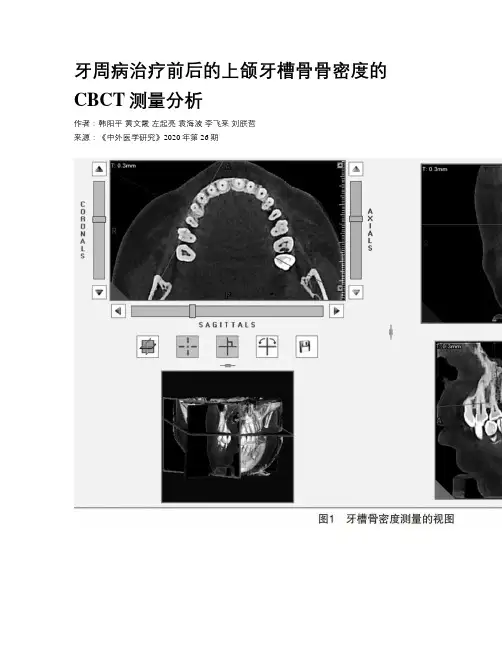

牙周病治疗前后的上颌牙槽骨骨密度的CBCT测量分析作者:韩阳平黄文霞左起亮袁海波李飞来刘朕哲来源:《中外医学研究》2020年第26期【摘要】目的:比較经过牙周基础治疗前后的上颌牙槽骨密度的变化情况,牙周炎症控制后,是否骨密度的变化可以作为判断牙周炎症控制的客观指标。

方法:随机选取10名慢性牙周病患者,测量上颌后牙牙周基础治疗前、后牙周袋的深度。

同时CBCT(锥体束CT)分别测量其上颌牙槽骨5个位点的皮质骨和松质骨的HU(Hounsfield Unit,灰度值)。

每组数据量为10×5=50个。

使用SPSS 22.0统计软件进行分析,采用配对t检验,检验水平为α<0.05。

结果:治疗前、治疗后牙周袋的深度为(5.16±0.96)、(3.60±0.66)mm;两组间差异有统计学意义(P=0.003)。

治疗前、治疗后皮质骨的HU值分别为979.48±114.80和1 074.48±119.57,差异无统计学意义(P=0.095)。

治疗前、治疗后松质骨的HU值分别为504.22±74.38和440.84±93.21,差异有统计学意义(P=0.037)。

结论:牙周病经牙周基础治疗后,炎症消退,牙周袋变浅,松质骨密度减少。